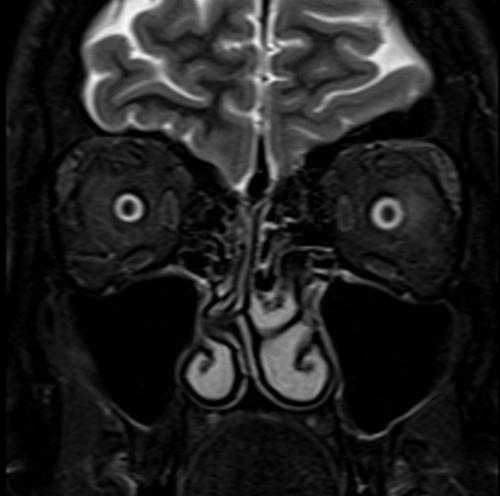

MRI Orbits STIR coronal images